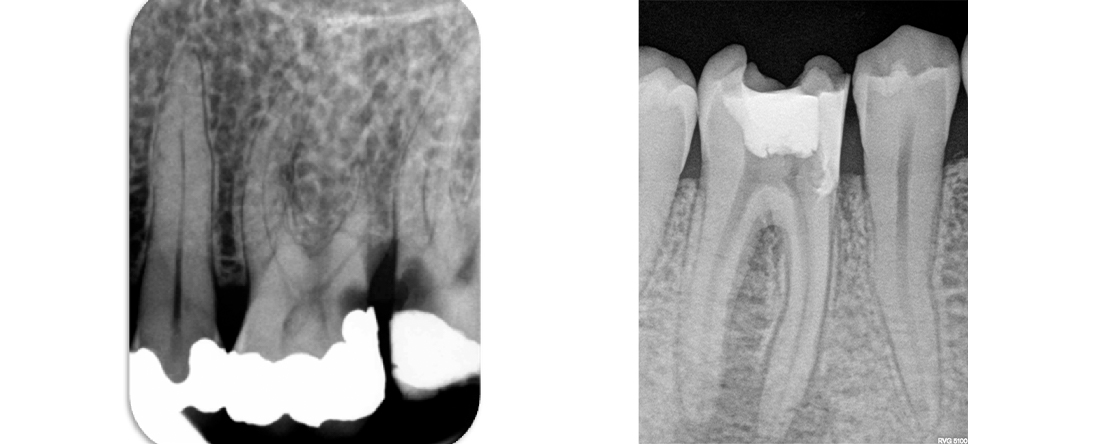

• diagnosticar corretamente as patologias pulpares e periapicais associadas a quadros de dor;

• realizar um tratamento endodôntico metódico, seguro e eficaz, que cumpra os princípios base da preparação químico-mecânica e obturação tridimensional canalar;